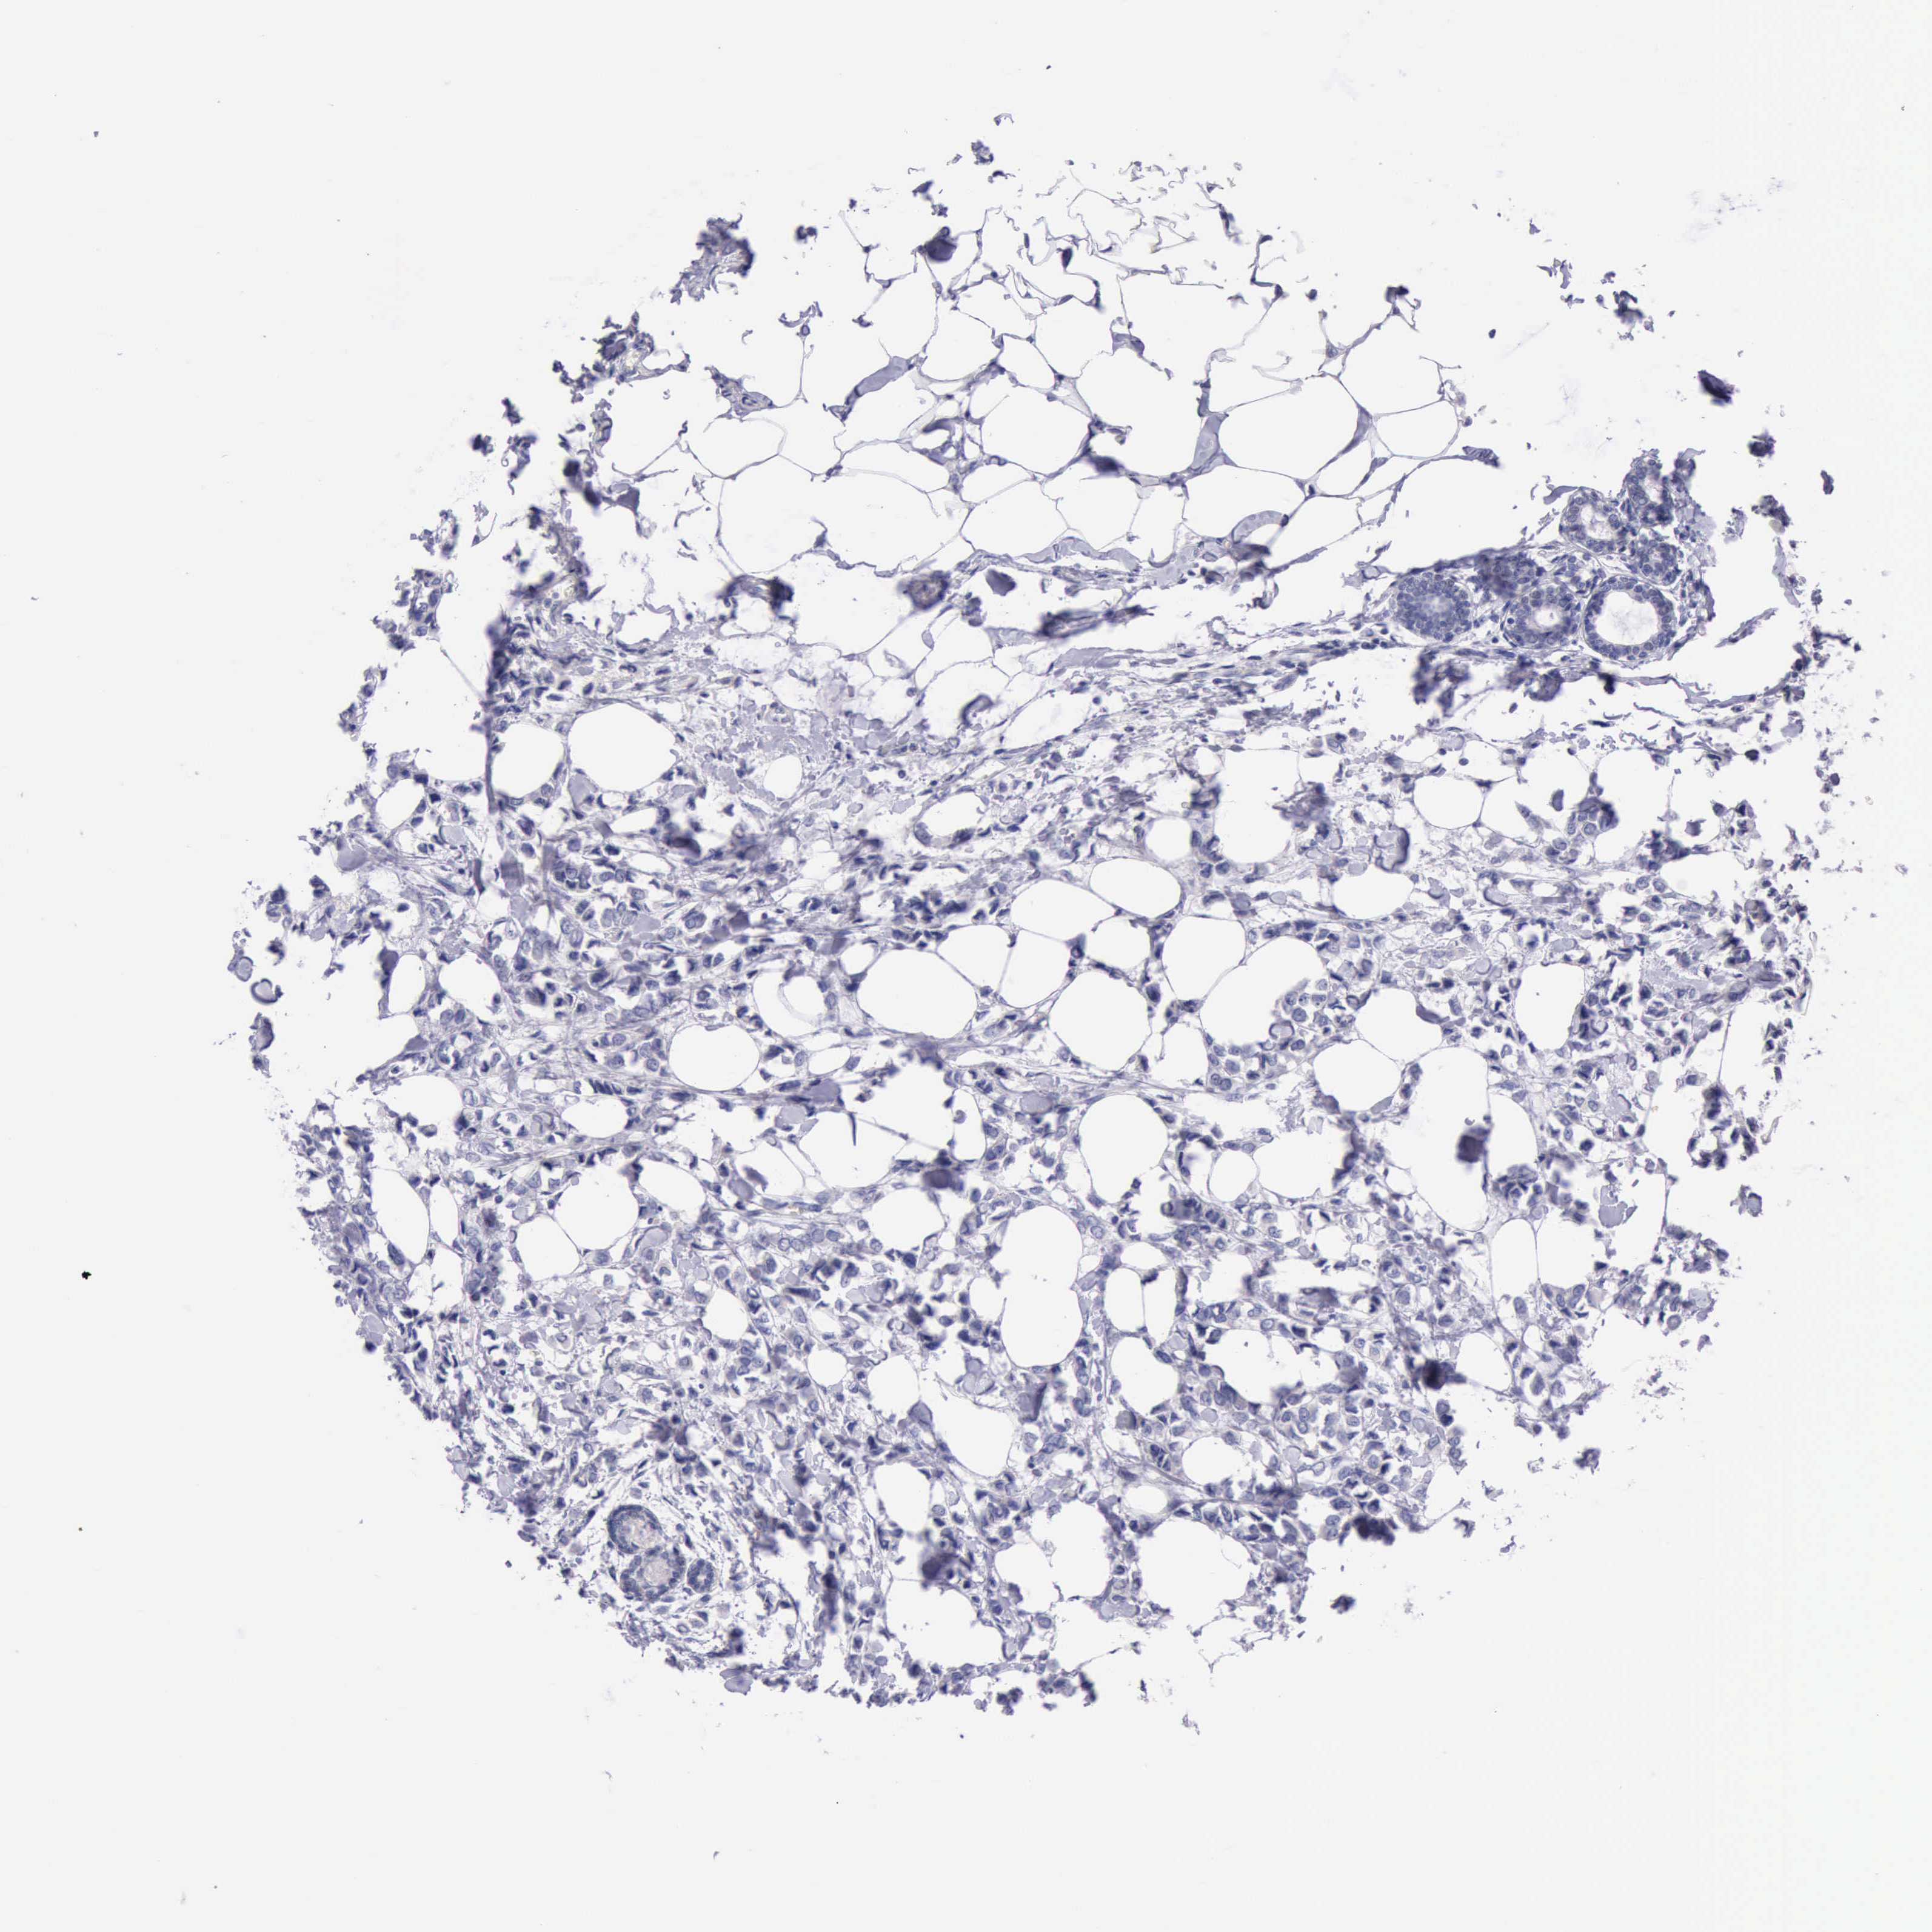

BRCA TCGA BRCA VALIDATION PROTEIN EXPRESSION

Breast cancer

Human cancer